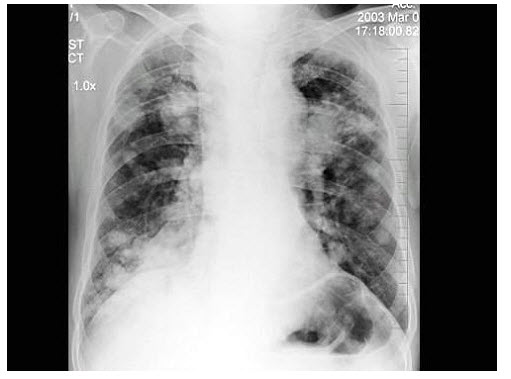

24、单项选择题

男,52岁,体检胸片如图,最可能的诊断是()

女,45岁,寒战、高热1周,WBC:1.8×109/L,胸片如图,应首先考虑()

A.肺结核